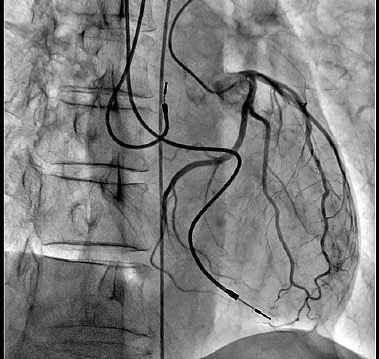

搭载SCORE PRO Advance的新Trinias系列拍摄的左冠状动脉造影图像

确实显示了清晰的支架图像。

接下来,就是把这个程序安装到设备中。森田、森、梅田多次促膝商谈,最终认识到,如果想制造出能够处理前所未有的庞大数据量的设备,就不能停留在过去的设计思想层次上。而找到解决对策的是森的部下——入职第七年的长谷川直纪。长谷川想到“如果处理时间较长,从拍摄对象运动到输出图像为止的这一过程会产生延迟。因此,我们需要设计出只要保存最低限度的必要数据,就能同时进行各种处理,快速完成处理的程序”(森)。森、梅田认识到这一方案的可行性,和森田、武田一起确定了规格。之后,长谷川和武田对细节进行了完善,2014年4月,新的图像处理引擎“SCORE PRO Advance”终于诞生。